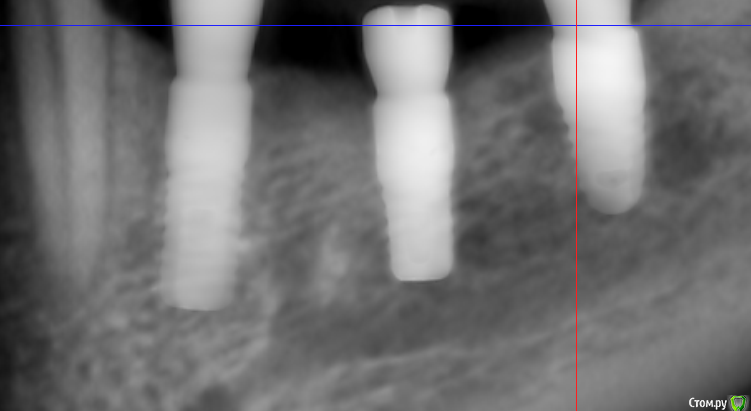

Sergiosse Опубликовано 4 декабря, 2019 Поделиться Опубликовано 4 декабря, 2019 Установил три импланта , средний вплотную к н.ч. каналу. После формирования ложа при зондировании перфора не было . на следующий день после операции онемение в области угла рта не проходит . Думал что из-за отёка. Сегодня пятый день. Изменений нет. Сильных болей нет , хотя пациентка принимает Кетонал. Пациентка сейчас в Москве , я я хочу попросить её чтобы она дошла до хирурга и на пару оборотов выкрутила средний имплант . вопрос Нужно ли это делать , как удостовериться, что это именно из—за импланта,сделать Кт? Отслойку лоскута делал осторожно,к выходу нерва не приближался , кровотечение и боли во время операции не было . Я думаю может быть медсестра (новенькая , неопытная )фарабефом придавила?=48001:тазеева2.png] Ссылка на комментарий

dok1 Опубликовано 4 декабря, 2019 Поделиться Опубликовано 4 декабря, 2019 Вообще по снимку как будто провалились слегка. Если это действительно так, то выкручивание большой пользы непринесёт 2 Ссылка на комментарий

Dmitry DK Опубликовано 8 декабря, 2019 Поделиться Опубликовано 8 декабря, 2019 Если вы все сделали по "инструкции" ( которая у вас на КТ ), наверняка имплантат оказался вплотную к каналу, но не думаю, что вы в него погрузились, но КТ нужно сделать для перестраховки.Скорее всего - фрезой залезли в канал ( он не обязательно должен кровить ), в таком случае выкручивание имплантата не поможет. Вопрос в том как сильно был поврежден сосудисто-нервный пучок, от этого будет зависеть динамика Ссылка на комментарий

Sergiosse Опубликовано 16 декабря, 2019 Автор Поделиться Опубликовано 16 декабря, 2019 В продолжение истории. Жалоб кроме, как на онемение нет. витамин В12 назначил. Думаю,продавил имплантом стенку канала,кагда давал торк. Через неделю увижу пациентку,какая дальнейшая тактика? Под нагрузкой от коронки не будет болей? странная верхняя стенка канала, с размытыми границами, остеопорз? Ссылка на комментарий

Дмитрий М Опубликовано 18 декабря, 2019 Поделиться Опубликовано 18 декабря, 2019 Мнения разделились. Вопрос: удаление импланта улучшит ситуацию? Выдавленная костная стенка всё равно останется внутри канала . Может быть лучше его выкрутить на пару оборотов ?что вам даст выкручивание на пару оборотов? по снимку не видно что имплантом провалились в канал, возможно только фрезой во время препарирования, и получили гиперкомпрессию от гемптомы в канале. возможно дело даже не в среднем импланте.покажите срезы ментального отверстия. после операции онемение в области угла рта не проходиттак понял, вы проводниковую анестезию делали? и во время операции пациент ничего не почувствовал, возможно ли что задели его во время отслойки лоскута? Ссылка на комментарий

Dmitry DK Опубликовано 27 декабря, 2019 Поделиться Опубликовано 27 декабря, 2019 Винт не в канале, очевидно, что фрезой задели. Выкручивание ничего не даст ( на нерв не давит). Удалять на случай разборок... Зачем?... Если разбор реально будет, на КТ все видно. Не переживайте, все наверняка восстановится через месяца 4, последней фрезой до нижней стенки вы видимо не дошли Ссылка на комментарий